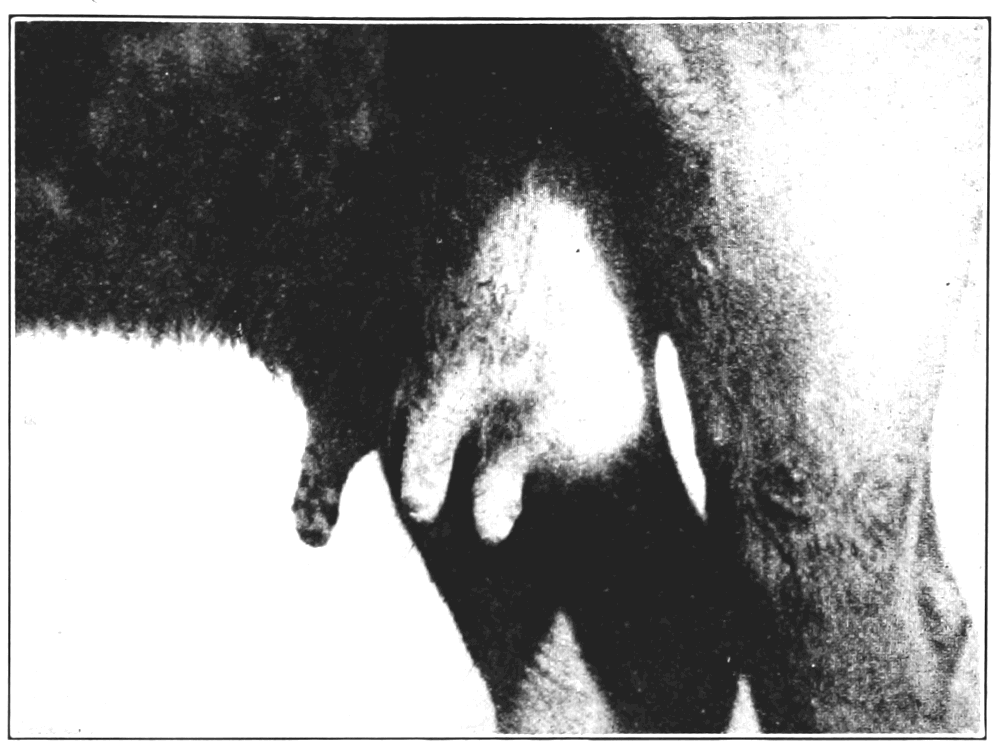

8½. Eruptions of foot and mouth disease on udder and teats of cow 95